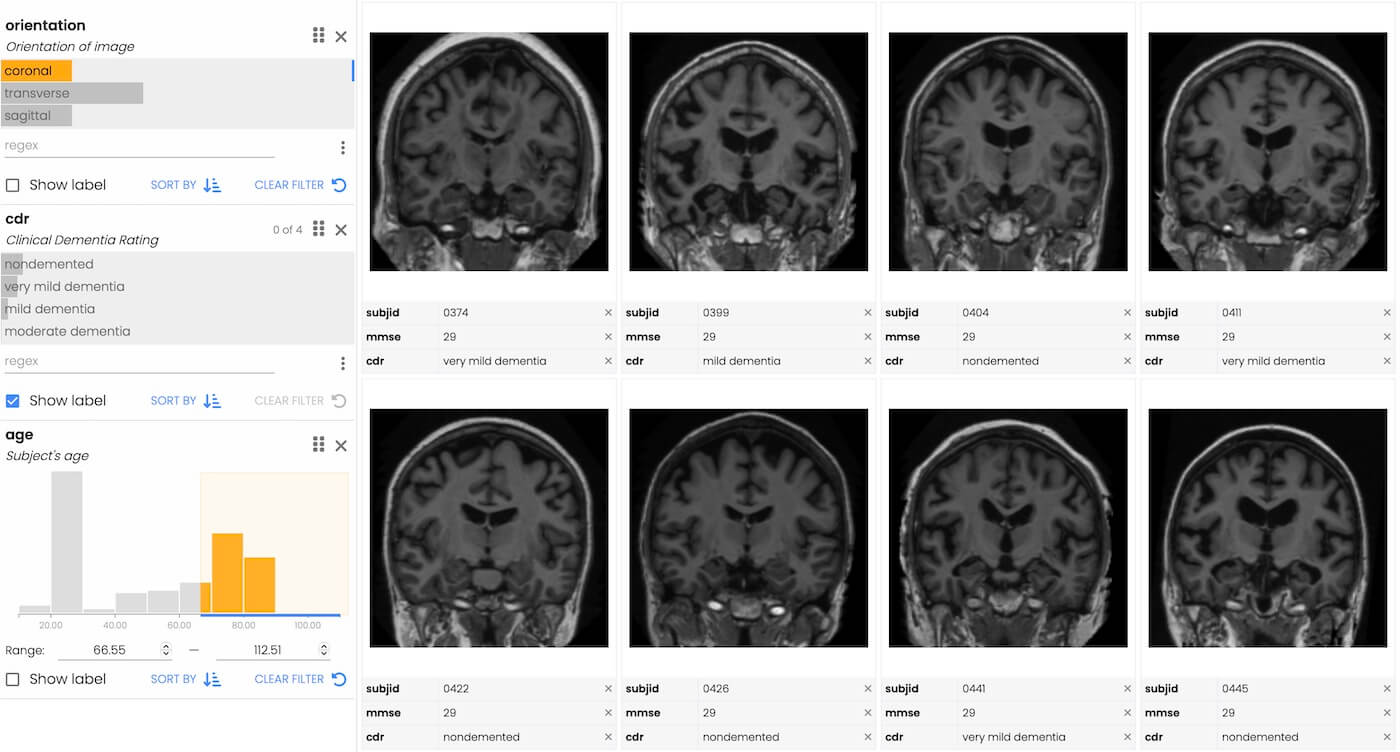

You can start with data in any form, but to use Trelliscope, you need to transform it into a data frame with one row per visualization and with columns representing metadata about each visualization. Trelliscope provides utilities for getting data into this form.

In the example below, we have a data frame that is already one row per image, and already has a column that points to the images. This contains images taken by the Mars rover Curiosity. We convert it into a "Trelliscope data frame". Note that the image column can also be a plot object.